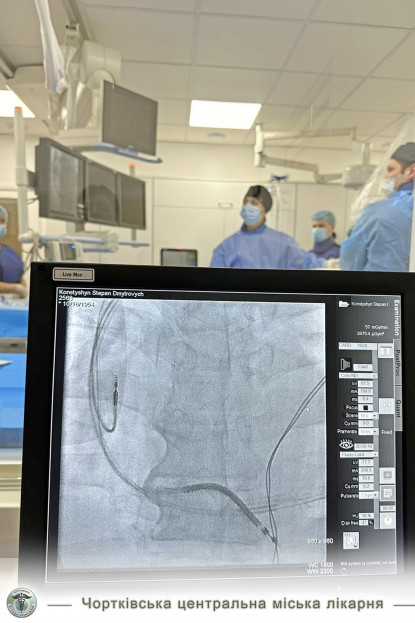

Днями у Чорткові відбулась історична подія для нашої медицини. У Чортківська центральна міська лікарня 69-річному пацієнту із Горішньої Вигнанки успішно імплантували в серце трикамерний кардіовертер-дефібрилятор. Оперативне втручання чортківські лікарі виконували спільно із фахівцями Національного інституту серцево-судинної хірургії ім. Амосова (м. Київ). Сам пристрій лікарня безкоштовно отримала від Міністерства охорони здоров’я, його вартість становить понад 300 тисяч гривень.

Як розповів сам пацієнт, раніше він двічі переніс інфаркт, з часом до проблем додалась тахікардія. Згодом чоловік все частіше скаржився на задишку, втомлюваність, загальну слабкість, зрештою йому діагностували повну блокаду лівої ніжки пучка Гіса, що стало показом до імплантації кардіостимулятора.

Операцію виконували лікар-хірург відділення лікування складних аритмій з рентгенопераційною Національного інституту серцево-судинної хірургії ім. Амосова Євген Перепека, а асистували йому фахівці Чортківської лікарні Тарас Сивак, Денис Хаблак, Марта Оробчук, Тарас Мазур, Роман Михальчук, Наталія Шишка.